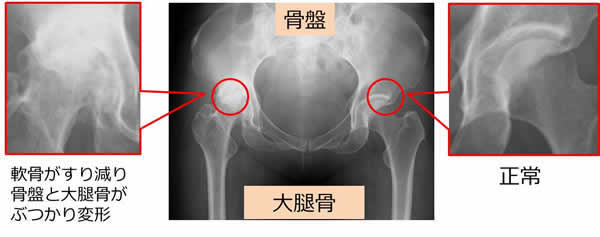

人工股関節全置換術は変形性股関節症や関節リウマチ、大腿骨頭壊死症などで痛みが生じ、薬物療法や理学療法で症状が改善しない場合に行われる手術です。

股関節は骨盤と大腿骨(太ももの骨)から出来ています。

健康な股関節の場合(向かって右側)は骨盤と大腿骨の間に隙間がありますが、変形性股関節症の場合(向かって左側)は骨盤と大腿骨の隙間がありません。

これが軟骨が磨耗している状態です。

人工股関節全置換術は、痛んだ関節の部分だけを取り除いて人工の関節に変える手術です。

骨盤と大腿骨の関節部分に白く写っている金属(チタン合金)を入れており、その間にポリエチレンとセラミックボールが入っています。